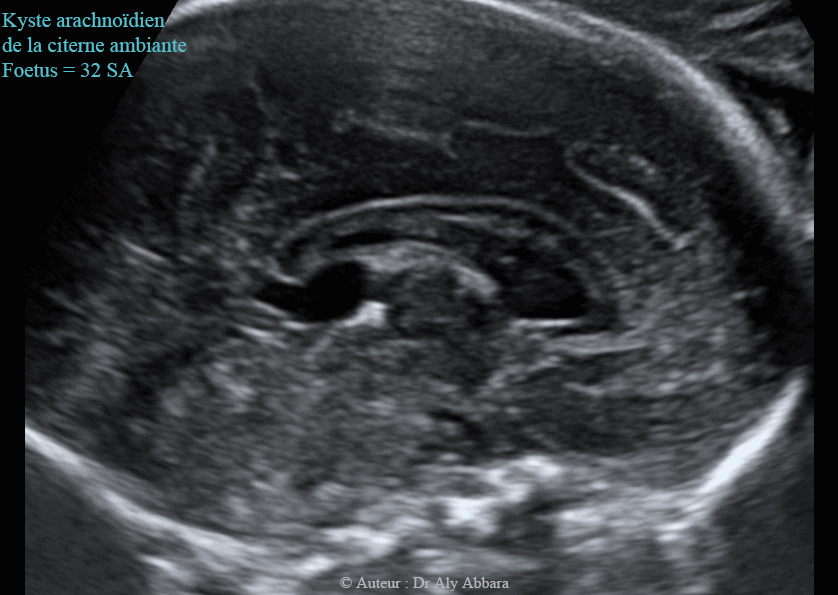

Echographie Kystes Arachnoidiens الكيسات العنكبوتية في الدماغ